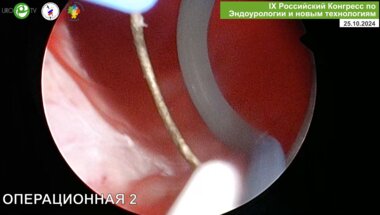

Севрюков Ф.А. - Биполярная энуклеация простаты (TUEB)

Севрюков Ф.А. - Плазменная трансуретральная энуклеация простаты (TUEB)

Севрюков Ф.А., Володин М.А. - Плазменная трансуретральная хирургия гиперплазии предстательной железы

Севрюков Ф.А. - Трансуретральная плазменная энуклеация простаты Olympus Plasma+ (объем простаты 80 куб.см)

Севрюков Ф.А. - Трансуретральная энуклеация аденомы предстательной железы биполяром ТУЭБ

Севрюков Ф.А. - Энуклеация гиперплазии предстательной железы больших размеров

Севрюков Ф.А. - Трансуретральная плазменная хирургия простаты

Севрюков Ф.А. - Трансуретральная биполярная плазменная энуклеация аденомы простаты (видеооперация)

Севрюков Ф.А. - Технические аспекты эндоскопического лечения аденом простаты гигантских размеров

Севрюков Ф.А. - От резекции к энуклеации гиперплазии предстательной железы

Севрюков Ф.А. - Трансуретральная хирургия гигантской гиперплазии простаты. 10-летний опыт

Севрюков Ф.А. - Биполярная энуклеация step by step

Живая хирургия. Севрюков Ф.А. Сорокин Н.И. - Трансуретральная энуклеация с использованием лазера и электрохирургической техники